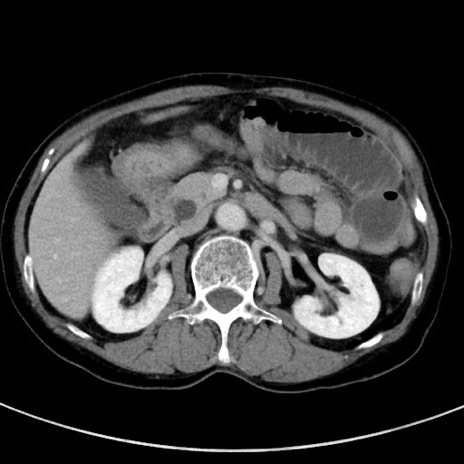

症例23(横断像)

【症例】70歳代女性

【主訴】下腹部痛・嘔吐

【現病歴】2日前より腹痛あり。昨日嘔吐あり。症状改善しないため来院。

【既往歴】胃GISTに対して胃部分切除後。

【身体所見】BT 37.1℃、BP 128/77mmHg、腹部:平坦・軟、下腹部に圧痛あり。

【データ】WBC 10200、CRP 0.31